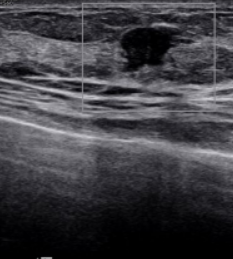

유방암 검사 비용은 보통 유방촬영(영산 진단)과 유방초음파(초음파 진료) 두 가지입니다.

유방초음파는 초음파 검사 시 병원마다 약간의 차이가 있지만 기본 10만 원부터 시작하며 보험 미적용 대상입니다.

하지만 초음파 검사 비용에 건강보험을 적용할 시 약 4~8만 원 정도만 내면 됩니다.(60% 수준 감경) 정확한 금액은 의료기관별로 다릅니다.

검사할 때 건강보험 혜택이 적용되는 기준은 따로 있습니다. 우선 가장 보편적으로 사용하는 흑백 영상 초음파 장비는 건강보험이 적용됩니다. 단, 진단 결과에 따라서 양성이냐 악성이냐 여부에 따라 최종 결정됩니다.

진료의사의 의학 판단에 따라 유방'액와부, 흉벽, 흉막, 늑골 부위에 질환이 의심되거나 이미 갖고 있는 질환으로 인해 경과 관찰이 필요한 경우 의사가 직접 시행한 초음파 검사에 한해 건강보험 적용이 됩니다.